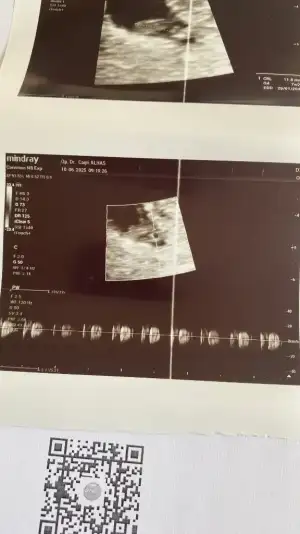

Önceden kimyasal ve boş gebelik geçmişim var,biraz riskli gruptayım diye bakıyorlar. 6+4 deyim. Kalp için gideceğiz bakalım kısmetseAaa hala neden baktırıyorsun ki betaa. Ben 14 mayısta transfer oldum 26 mayıs test günümdü. En son 28 inde baktırdım bida baktırmadım. Kalp atışı için mi gideceksin sende. Kaç haftalıksın

Geldik bizde şimdi hastaneye bekliyoruzzzGünaydın teyzesiiiiikalp atışını duyduk. 6+4 de . Sen gittin mi

Çok sevindim gözünüz aydııınnGünaydın teyzesiiiiikalp atışını duyduk. 6+4 de . Sen gittin mi

Çok sevindim gözünüz aydııınnultrason fotosu da verdi mi atsanaa